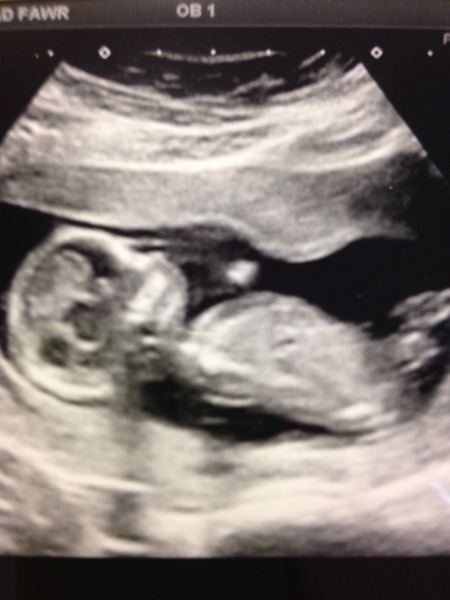

I'll catch up on the thread in a second, but here's baby unthought who was remarkably well behaved in the scan.